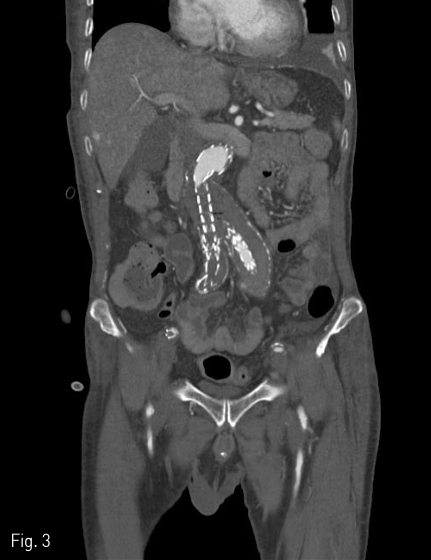

2018년 좌측발의 통증과 색깔변화를 주소로 내원하여 시행한 조영증강 CT(Fig. 1)상에서 발견된 복부대동맥 및 양측 장골 동맥류에 대해 InCraft(Cordis, Milpats, US)를 이용한 EVAR 치료(Fig. 2)를 받은 환자로, 술후 퇴원전 조영증강 CT(Fig. 3)상에서 우측 장골 분지 인조혈관이 폐색된 소견을 보였다.

Fig 3

CT angiography obtained 4 days after EVAR shows thrombo-occlusive change of right limb graft.